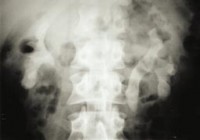

I always enjoy the Image Challenge Contest at The New England Journal of Medicine, time ago there was a similar picture of this:

U P D A T E: A nice comment and correct answer by Drmikeunoe

We can see generalized osteopenia, widening of the diploetic space, and thinning of the outer table.

This characteristic “hair on end” appearance of the outer table is compatible with the presence of massive hyperplasia of the bone marrow, as can be seen in the homozygous state of beta-thalassemia (i.e. thalassemia major).

Beta thalassemia syndromes are a group of hereditary disorders characterized by a genetic deficiency in the synthesis of beta-globin chains (adult hemoglobin usually is α2β2) resulting in excess α-chains and severe transfusion-dependent anemia, thus causing bone marrow hyperplasia.